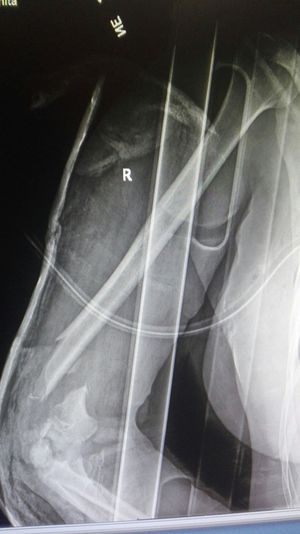

Right humerus ,dislocalt supracondyler fracture.

Xray

Fracture

Humerus